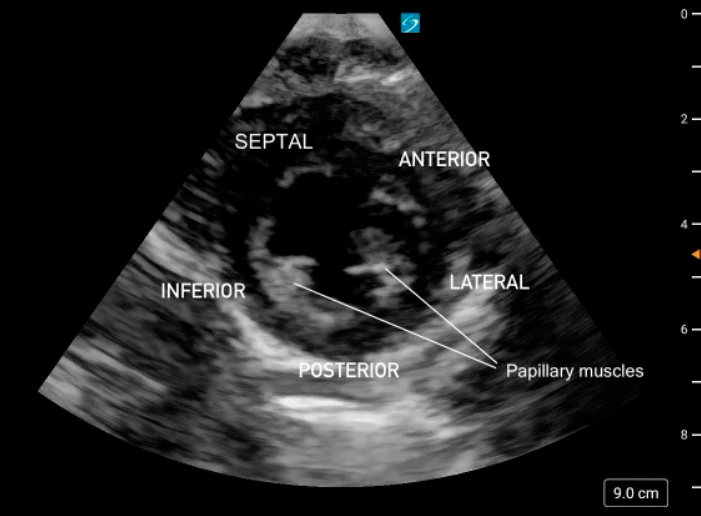

The PSAX view provides a cross-sectional image of the LV, allowing simultaneous visualization of multiple walls. It is the preferred view for global assessment of LVfx and RWMAs. This view is useful for assessing wall motion across the anterior, lateral, posterior, inferior, and septal segments, all seen in a single plane at multiple levels (basal, mid, apical) (figure 11).

A circular LV cavity indicates you’re on-axis, while an oval or elliptical shape suggests you’re off-axis and should adjust your probe angle for a true short-axis view.

Figure 11. PSAX at the mid-papillary level with left ventricular walls labeled.